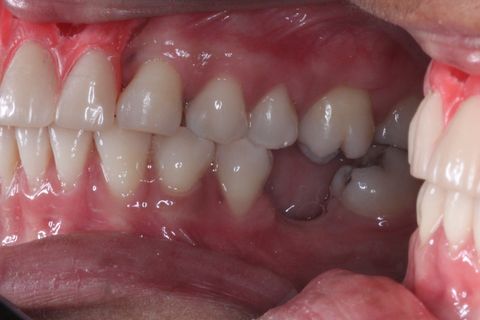

Foto Inicial. Paciente fazendo uso de Prótese Parcial removível.

Foto Perfil (uso de espelho). Lado esquerdo

Foto Perfil (uso de espelho). Lado Direito